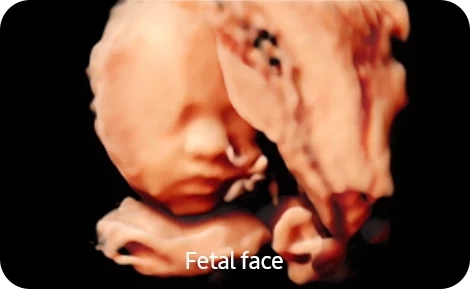

• Smart 4D- Модуль объемного сканирования в реальном времени Smart 4D с расширенным набором инструментов для обработки и представления объемного изображения;

• Realistic Vue- Модуль реконструкции объемного изображения с возможностью перемещения виртуального источника освещения Realistic Vue. Необходим модуль 4D;

• Crystal Vue- Модуль визуализации объемного изображения, с усиленной способностью к контрасту за счет использования различных степеней прозрачности и подсветки структур Crystal Vue;

• Crystal Vue Flow- Модуль визуализации объемного изображения, с усиленной способностью к контрасту за счет использования различных степеней прозрачности и подсветки структур, c одновременной реалистичной визуализацией объемного кровотока Crystal Vue Flow;